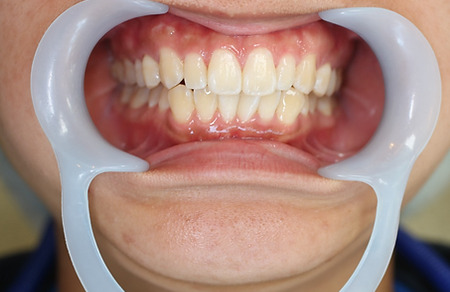

1矯正・マウスピース【治療例1】

治療前

治療後